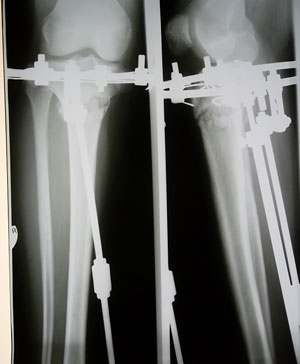

Костная мозоль зреет хорошо, к концу месяца можно приезжать на снятие аппаратов.

У Вас по 2 спицы в каждом кольце осталось???

SAM_4391.JPG

SAM_4389.JPG

Да, у меня на каждой ноге по две спицы, я хорошо себя чувствую, легче двигаюсь и намного легче поднимаюсь по лестнице)))) solnce solnce solnce

Я так рада, что снимки все же пришли))))